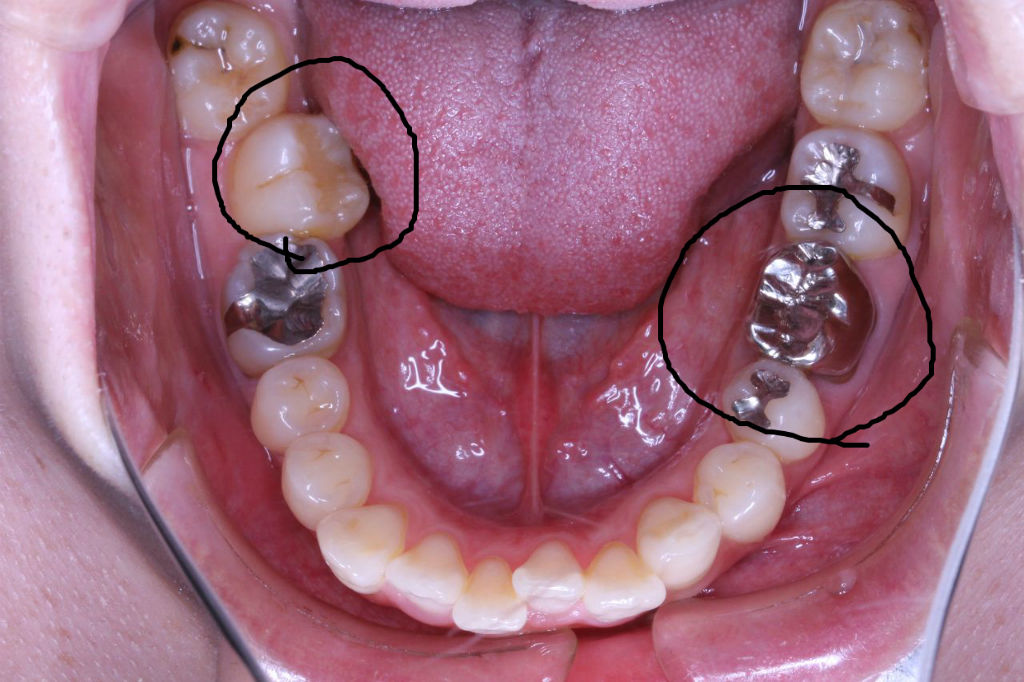

治療開始から3年経過した現在の状況です

もともとは

上の歯列はどうでしょうか?

その患者さんの数年前の画像です

現在は他のクリニックで歯列矯正を一切しない方法で治療を開始しており、かみ合わせがおかしくうまくいっていないような気がするとのことでコメントを求めての来院でした。